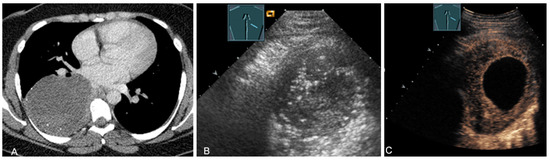

1.4.1. Hematomas of the Chest Wall

Hematomas of the chest wall are usually the result of blunt or penetrating trauma or arise after thoracic surgery. Spontaneous hematomas are found in rare cases in anticoagulated patients or in patients with coagulopathies and/or malignant tumors of the chest wall. The sonographic image depends mainly on the age or degree of organization of the hematoma. Whereas fresh hematomas are inhomogeneously hyperechoic due to their high erythrocyte content, organized hematomas are usually inhomogeneously hypoechoic or even nearly anechoic. CEUS is helpful in the differentiation of solid tumors (Figure 1).

Figure 1.

A patient after surgery for a bronchial carcinoma with a palpable chest wall tumor (A). B-mode US reveals a heterogeneous echogenic mass (B) without enhancement on CEUS (C), consistent with hematoma of the chest wall.